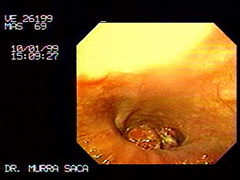

Imagen del cardias, Paciente Masculino 69 años:

Con disfagia progresiva, perdida de peso 20 libras y sialorrea, presenta Carcinoma del cardias y fondo, ver imagenes siguientes.